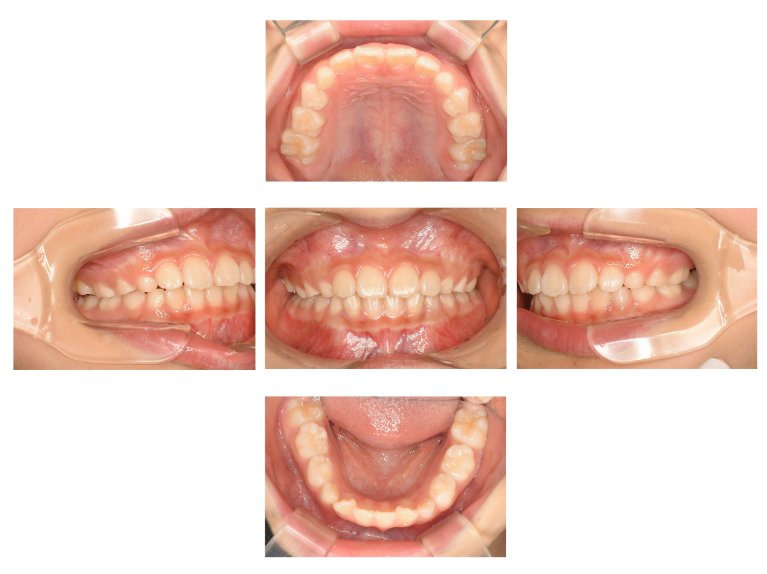

術後

| 治療名 | 小児矯正 |

|---|---|

| 治療説明 | 将来の歯並びが悪くなる可能性が非常に高いと判断されたため、上顎に急速拡大装置、下顎にリンガルアーチを用いて小児期の矯正治療を行いました。大人の歯が映えるスペースを確保し、上下の顎のアンバランスも改善できました。 |

| 治療回数・期間 | 1年 |

| 副作用とリスク | 大人の歯の位置や方向を完全にコントロールできない可能性があり、追加の成人矯正が必要になる可能性があります。治療期間が長くなる可能性、複数回の装置作成が必要となる可能性があります。 |

| 料金(税込) | 550,000円 |